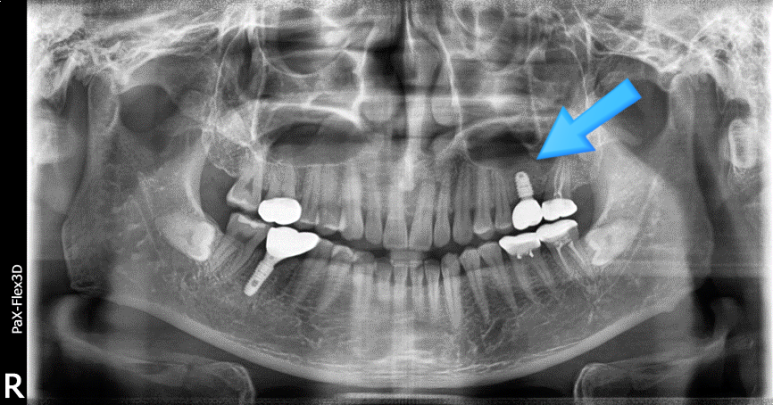

잇몸뼈 부족으로 상악동거상술을 통한 뼈이식 진행한 환자분의 x-ray

물론 수술 전 CT 검사를 통해 막 상태를 어느 정도 확인할 수 있기 때문에 검사결과상 이상한 부분이 관찰되면 시술 전 이비인후과 진료를 먼저 보실 수 있도록 안내해 드리고 있습니다.